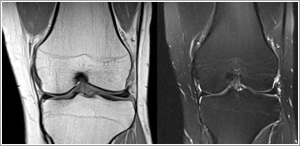

Orthopedic MRI

Only MRI has the ability to non-invasively image the soft tissue structures within the joints and extremities. This allows early and accurate diagnosis of potentially serious injuries to the bones, muscles, tendons, ligaments, and fibrocartilage following sports injury or accidental trauma.